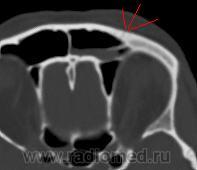

Результат МСКТ-костей черепа и головного мозга:

На станции вроде бы всё настроил, чёткость несколько сбилась изображений, вообще ссадина была слева и слева видно в ячейке лобной пазухи жидкость плотность крови(55HU), была сделана реконструкция с интервалом 1,5мм. Перелмо передней стенки ячейки лобной пазухи, можно даже так сказать "трещина" и гемосинус: